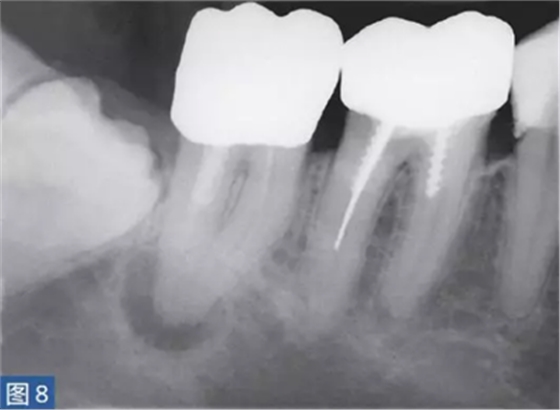

急性根尖周膿腫(AAA acute apical abscess)

急性根尖膿腫(圖8 和9)是一種局部的或者彌漫性的液性病變。由壞死牙髓產(chǎn)生的微生物和非微生物刺激所引起的嚴(yán)重炎癥反應(yīng)造成了根尖周組織的破壞?;颊咄ǔ1憩F(xiàn)出中度至重度疼痛,根據(jù)嚴(yán)重程度還可能出現(xiàn)發(fā)熱和白細(xì)胞增多的全身癥狀。

臨床診斷顯示牙髓電活力測(cè)試結(jié)果陰性。叩診和觸診通常會(huì)引起疼痛。如果膿腫僅限于骨內(nèi),則不出現(xiàn)腫脹癥狀。放射學(xué)檢查,根尖周組織表現(xiàn)從無(wú)變化到發(fā)生明顯變化。

圖8:47 牙齒AAA。術(shù)前X 線片。患者就診時(shí)有發(fā)燒癥狀,且叩診和觸診疼痛明顯。